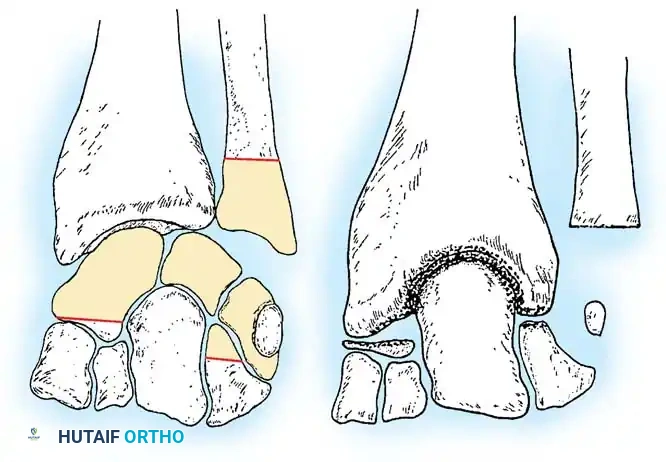

Fig. 4-22: (A) Schematic diagram depicting the bone to be resected to accomplish capitate-radius arthrodesis. (B) Postoperative schematic. The proximal pole of the capitate and the distal surface of the radius have been denuded of cartilage. A portal is established in the distal radius, and the congruous trabecular surfaces are apposed.

Step-by-Step Surgical Procedure

- Approach the wrist dorsally as described in Technique 4-13.

- Perform a proximal row carpectomy: Excise the entire lunate and triquetrum. Remove approximately 80% of the proximal scaphoid and a portion of the proximal hamate.

> Clinical Pearl: It is vital to retain the distal portion of the scaphoid and hamate to maintain the structural integrity of the distal carpal row and prevent proximal migration or destabilization of the remaining carpus. - Aggressively denude the articular cartilage from the lunate fossa of the distal radius and the proximal pole of the capitate.

- Appose the capitate directly into the prepared fossa of the distal radius.

- Fixation can be achieved with a short-bend AO dorsal plate, or alternatively, with crossed Kirschner wires/staples supplemented with abundant cancellous bone graft.